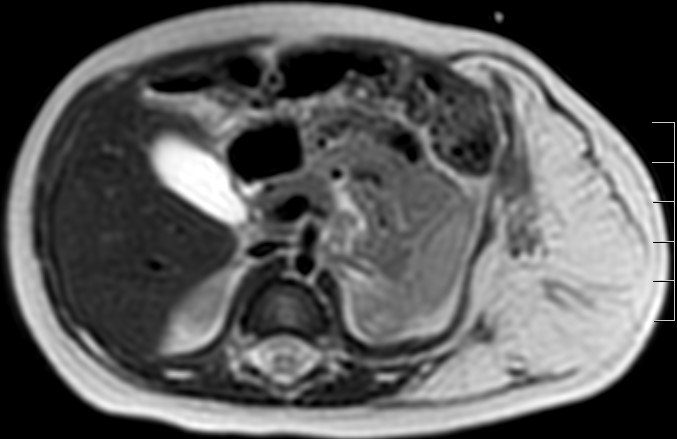

Monday Morning Case 5 month old Girl With A Palpable Mass In The

Figure 1 From Primary Malignant Rhabdoid Tumor Of The Liver In A 5